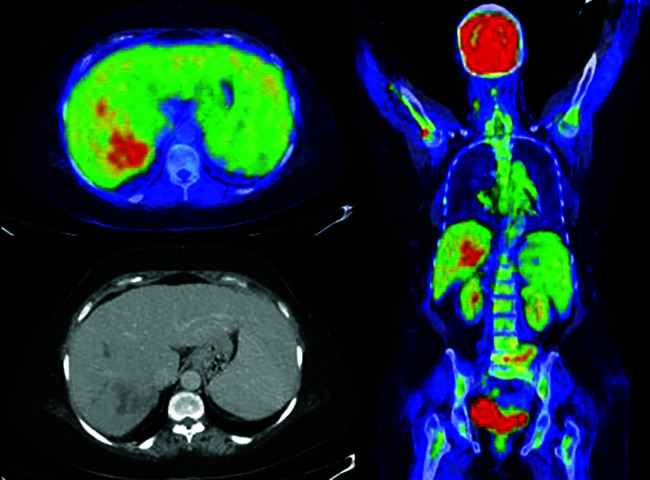

Results: Among the cohort of 51 patients, primary HCC was detected on FDG PET-CT in 43 individuals representing true-positive cases. Conversely, FDG PET-CT was unable to detect HCC in 8 cases, representing false-negative. Out of 51 patients, 74.5% of HCC cases exhibited multifocal pattern. The maximum standardized uptake value (SUV max) of the primary malignant site ranged from 1.9 to 16.1, with a mean of 3.7 ± 2.8. The FDG PET-CT revealed abnormal sites of the uptake outside liver in 23 individuals. The research confirmed the tumor recurrence in four previously treated patients. In the conducted investigation, FDG PET-CT showed 84.3% sensitivity for the diagnosis of HCC.